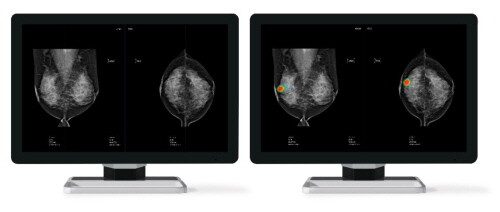

| ▲루닛의 유방암 진단 보조 AI 솔루션 ‘루닛 인사이트 MMG’ (사진=루닛 제공) |

루닛의 유방암 진단 보조 AI 솔루션인 루닛 인사이트 MMG는 국내 식약처 허가 및 유럽 CE 인증을 획득해 현재 전 세계 20개국 이상의 헬스케어 기관에서 활발히 사용되고 있다.